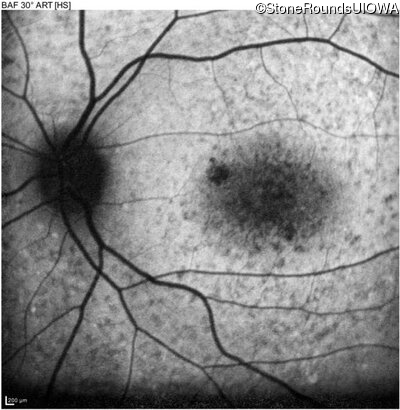

AR Stargardt Disease (IIA)

Age at visit: 15 years

This 15 year old female recalls not being able to see the black board in 2nd grade despite sitting in the 2nd row.

AR Stargardt Disease ABCA4 Val256Val GTG>GTT His1118Asp CAC>GAC AR